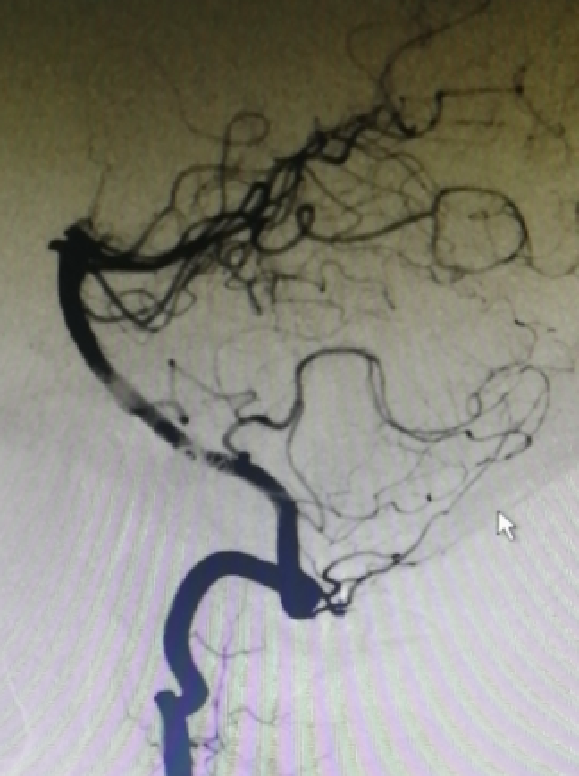

6个月复查

病例2

男性,55岁

头痛1周

SAH H&H II

如何保护PICA?

远端狭窄处理?

一般选择ped3.5x35,最后选用3.75x35(推挤)

血管测量

三维测量有误差!

Axium3d38 2d26 24

术后1周(酒后)

单抗一周,改双抗